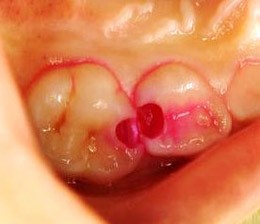

虫歯の治療では、「う蝕検知液」という専用の検査薬を使用します。この検知液は、虫歯菌に感染した部分のみを着色し、健康な部分との区別が可能です。

そのため、着色された部分だけを削ることで、健康な歯をできるだけ残す治療が行えます。